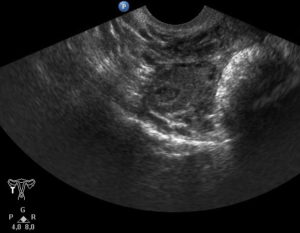

Определить наличие кистозного образования в половой железе можно в ходе гинекологического осмотра и УЗИ, а вот конкретно сказать, что делать с данной опухолью можно только после определения ее разновидности, до этого момента женщина с любым типом кисты берется на учет и наблюдение за развитием, как новообразования, так и плода.

Как правило, кисты небольших размеров никак себя не проявляют. Они не ухудшают качество жизни, при хороших обстоятельствах не влияют на работу репродуктивной системы и, соответственно, не являются преградой для зачатия. Поэтому женщины узнают об их наличии уже во время первого УЗИ по беременности.

На этом этапе диагностики врач может лишь предположительно указать характер патологии, ориентируясь только на ее внешние проявления. Однако часто они имеют вид безопасных образований, но одновременно с этим носят злокачественный характер. Поэтому определить возможные риски с высокой точностью при помощи одного только УЗИ при беременности практически невозможно.

Так как во время беременности заболевание никак не проявляется и не сопровождается никакой симптоматикой, то диагностировать его можно только при плановом УЗИ. Необходимо проходить обследование у квалифицированного специалиста ультразвуковой диагностики, потому что кисту яичника у плода легко перепутать с патологиями кишечника (такие случаи встречались).

Ультразвуковое исследование позволяет не только диагностировать наличие заболевания, но также его локализацию, размеры, эхоструктуру. Также УЗИ дает возможность отслеживать изменения размеров кисты как в сторону увеличения, так и ее регресс.

Благодаря УЗИ можно заранее обнаружить патологию. Киста яичника у плода при подобном обследовании выявляется часто.

Киста яичника у плода — образование, которое сложно рассмотреть во время беременности. Для этого врачи прибегают к ультразвуковому обследованию. Данный метод позволяет им рассмотреть образование в увеличенном виде на мониторе.

Современная ультразвуковая диагностика позволяет не только определить наличие опухоли у зародыша, но еще оценить ее структуру и размеры. На основе этой информации врач может составить прогноз. Чаще всего заболевание проходит спонтанно, за несколько месяцев после родов.